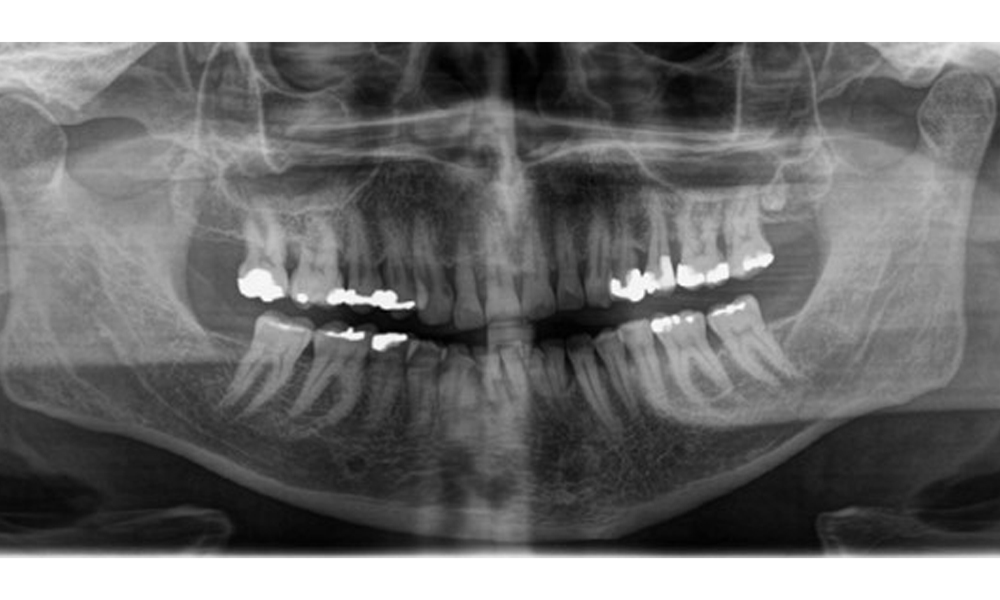

There is fully dentulous adult dentition with generalized bone loss of between 20-50% and multiple areas of vertical bone loss. Radiological examination revealed no visible caries. (Fig. 7)

Panoramic X-ray image showing generalized radiological bone loss with multiple vertical defects of between 20% to 50%. © Dr R. Krapf

Fig. 7 Panoramic X-ray image showing generalized radiological bone loss with multiple vertical defects of between 20% to 50%. © Dr R. Krapf